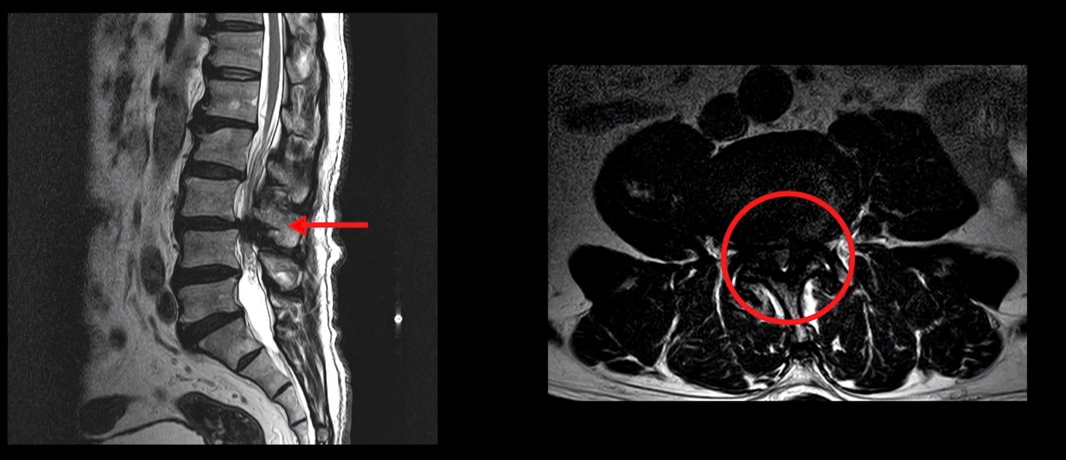

이 환자분은 3,4번에 심한 중심성 척추관협착증이 있습니다. 후관절과 황색인대가 모두 두꺼워진 진짜 협착증으로 신경이 지나가는 척추관이 많이 좁아져 있고 증상도 조금만 걸으면 발바닥과 허벅지가 저리고 다리에 힘이 빠져 서있을 수 없어 아무데라도 주저 앉아야 하는 신경성파행 증상, 즉 진짜 협착증 증상을 보이시는 환자분이십니다. 이런 환자분이 재활치료로 어떻게 또 얼마나 호전될 수 있을까요? 환자분의 얘기를 직접 들어보겠습니다.